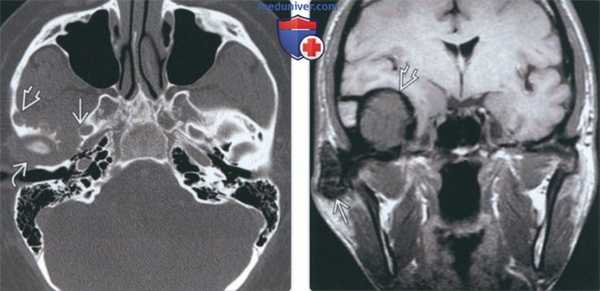

(Слева) При аксиальной КТ в костном окне определяется расширение суставного пространства правого височно-нижнечелюстного сустава, также видны множественные эрозии округлой формы в прилежащих отделах основания черепа с поражением скуловой дуги и большого крыла клиновидной кости выше наружного края овального отверстия.

(Справа) При МРТ Т1ВИ в корональной проекции визуализируется гипоинтенсивное объемное образование правого ВНЧС с «ободком» низкой сигнальной интенсивноаи. Также визуализируется гипоинтенсивное экстрааксиальное объемное образование в средней черепной ямке, тесно прилежащее к интракраниальным структурам, с таким же гипоинтенсивным «ободком» по периферии.

(Справа) При МРТ Т1ВИ в корональной проекции визуализируется гипоинтенсивное объемное образование правого ВНЧС с «ободком» низкой сигнальной интенсивноаи. Также визуализируется гипоинтенсивное экстрааксиальное объемное образование в средней черепной ямке, тесно прилежащее к интракраниальным структурам, с таким же гипоинтенсивным «ободком» по периферии. (Слева) При MPT T1BИ FS с КУ в аксиальной проекции, выполненной пациенту с пигментным ворсинчато-узелковым синовитом (ПВУС), в расширенном суставном пространстве правого ВНЧС и вокруг него визуализируются многочисленные узлы с гипоинтенсивным сигналом. Обратите внимание, что контрстаное усиление выражено минимально.

(Слева) На аксиальной КТ в костном окне определяется расширение суставного пространства правого ВНЧС с наличием множественных округлых эрозий прилежащих отделов основания черепа с вовлечением внутреннего края скуловой дуги и большого крыла клиновидной кости вплоть до наружного края овального отверстия.

(Справа) На корональной МРТ (Т1 ВИ) определяется гипоинтенсивное объемное образование В правого ВНЧС с «ободком» на периферии еще более низкой интенсивности, продолжающееся во внемозговое объемное образование средней черепной ямки с похожим ги-поинтенсивным «ободком» на периферии.